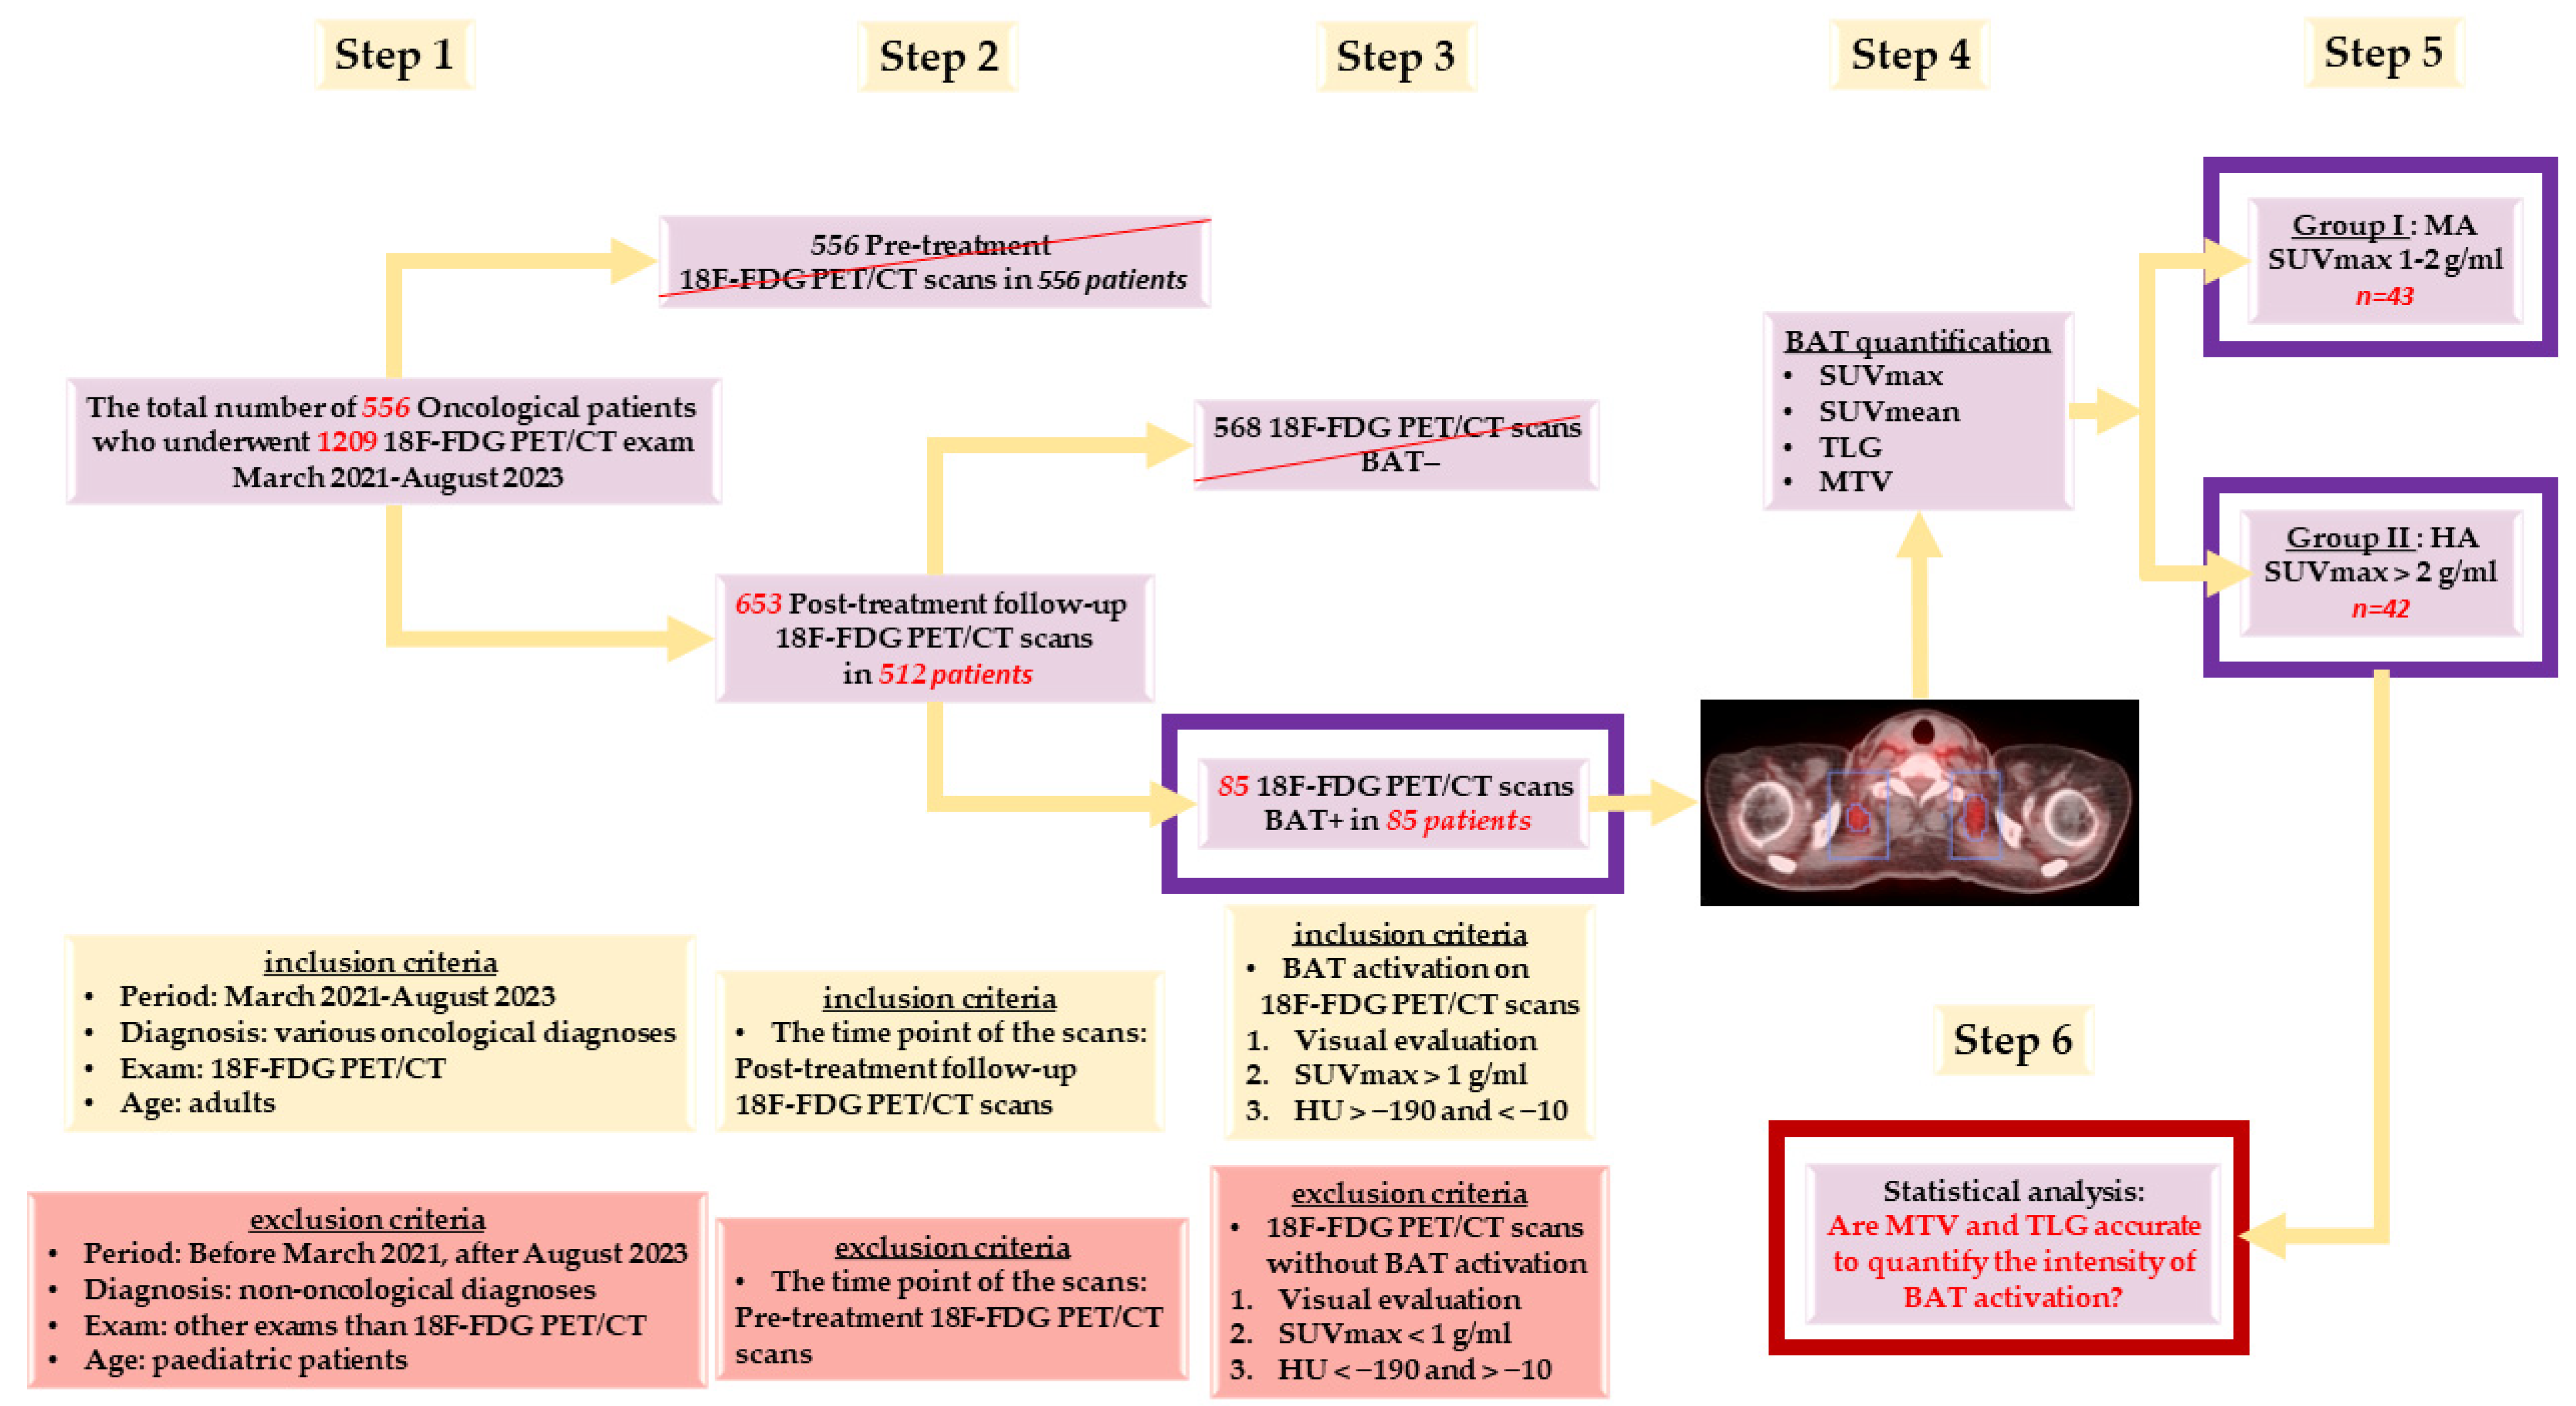

2. Materials and Methods

2.1. Patients

2.3.1. Visual Determination of BAT Activation

2.3.2. Quantitative Confirmation of BAT Activation

2.3.3. Quantification of BAT Activation Intensity in Every BAT+ Scan

- Total BAT SUVmax in g/mL (Tot SUVmax) = We chose the greatest value of SUVmax measured in all of the VOIs drawn from all BAT localisations;

- Total BAT SUVmean in g/mL (Tot SUVmean) = We calculated the mean of all SUVmean values measured in all of the VOIs in all BAT localisations;

- Total BAT TLG in cm3 × g/mL (Tot TLG) = We calculated the sum of all TLG values measured in all of the VOIs drawn from all BAT localisations;

- Total BAT MTV in cm3 (Tot MTV) = We calculated the sum of all MTV values measured through the ratio of Tot TLG/Tot SUVmean in all of the VOIs drawn from all BAT localisations.

- -

- Group I: Patients with BAT moderate activation (MA)—Tot SUVmax between 1–2 g/mL;

- -

- Group II: Patients with BAT high activation (HA)—Tot SUVmax > 2 g/mL.

2.4. Statistical Analysis